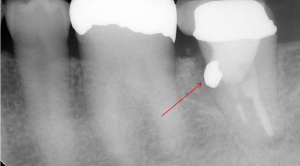

「この歯には、長くて太い金属の土台が入っていて、この金属の土台を取ろうとすると歯が割れてしまうので、治療ができません。なので抜歯です。」

確かに長くて太い金属の土台を除去するのは難しい治療と思います。

ほんの少しでも操作を間違えれば、歯を割ってしまったり歯の根に穴を開けてしまったりします。

地味ーに少しずつ少しずつ金属の土台を削って、少しでも心配ならレントゲンを撮ってと手間暇惜しまずかけて除去したのです。

歯を全く削らず、しかも短時間で出来るのです。症例にもよりますが、だいたい数分でできます。以前の様に地味ーに削っていく方法だと20分以上かかったものです。